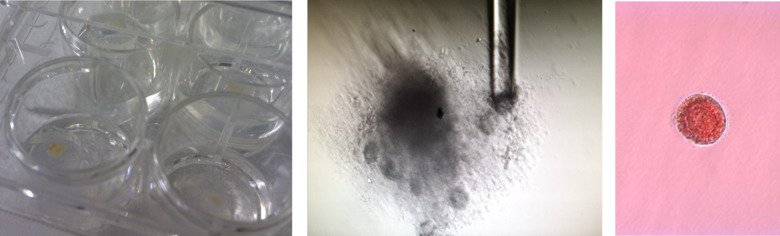

Utveckling av vitro-modeller som efterliknar äggstockar

Vi använder äggstocksvävnad för att utveckla in vitro-modeller som efterliknar äggstocken eller kan härma dess olika funktioner. Sådana modeller är nödvändiga för att på ett humanrelevant sätt bedöma toxiciteten hos kemikalier i laboratoriet, utan användning av försöksdjur. Dessutom kan modeller som efterliknar äggstockar i framtiden användas för att mogna äggceller in vitro.

“Culture of human ovarian tissue in xeno-free conditions using laminin components of the human ovarian extracellular matrix” Hao et al. 2020 J Assist Reprod Genet